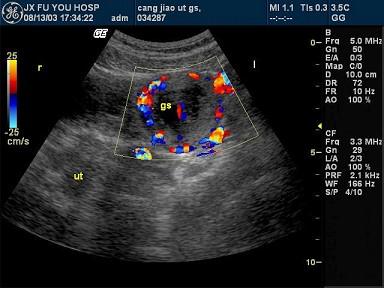

问题 女性,28岁,停经46天,阴道不规则出血5天。血HCG68μg/ml。结合超声图像,最可能的诊断为?(?)

选项 A.畸胎瘤 B.附件炎性包块 C.子宫浆膜下肌瘤 D.宫外孕 E.囊腺瘤

答案 D